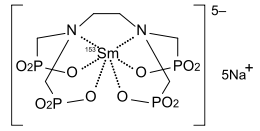

Radiothérapie métabolique palliative

Dans la radiothérapie métabolique palliative, des médicaments radioactifs sont injectés au patient. Comme pour la radiothérapie externe, le remodelage osseux et les inflammations dans le voisinage des métastases sont freinés par la radiothérapie métabolique. L'efficacité de la radiothérapie métabolique pour les métastases de cancer du sein et de la prostate a été démontrée par de nombreuses études. Le taux de réponses se situe à environ 70 % des patients traités. On obtient une disparition complète de la douleur pour environ 30 % des patients. L'apaisement des douleurs a lieu environ 48 heures après le traitement avec le 186rhénium ou le 153samarium et dure entre un et douze mois[135]. Dans les deux à quatre premiers jours, on obtient chez 10 %[136] à 30 %[137] des patients une accentuation initiale durant en moyenne trois jours des douleurs[137]. Selon le type de tumeur primitive, on peut utiliser encore d'autres radionucléides.